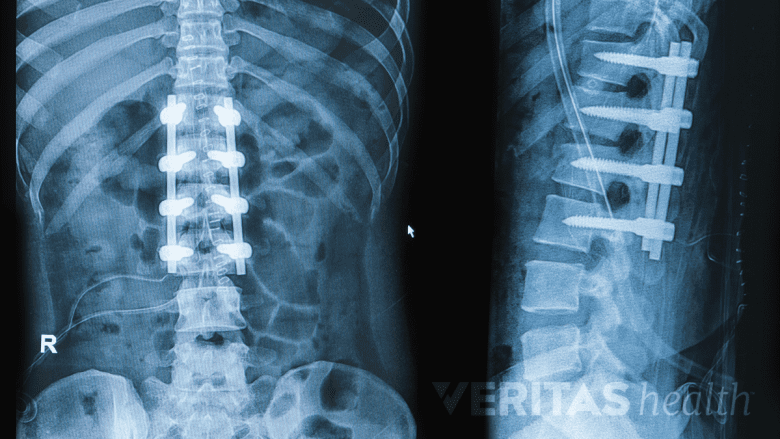

Fusion. This spinal surgery permanently fuses two or more adjacent vertebrae so that they grow together at the spinal joint and form a solid bone that no longer moves. Modern surgical approaches and instrumentation—rods, screws, hooks, and/or wires placed in the spine—have enabled spinal fusion surgeries to achieve better curvature correction and faster recovery times than in the past.

An advantage to spinal fusion surgery is that it has a long-term record of safety and efficacy for treating scoliosis. While a drawback to the procedure is that any fused vertebrae will lose mobility, which can limit some of the back’s bending and twisting, today’s spinal fusions tend to fuse fewer vertebrae and maintain more mobility than in the past.